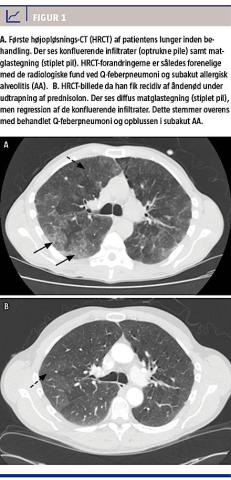

En højopløsnings-CT (HRCT) af lungerne viste smånodulære forandringer, multiple konfluerende infiltrater samt matglastegning. En udvidet lungefunktionsundersøgelse viste en restriktivt nedsat lungefunktion med en diffusionskapacitet på 60% af det forventede.

Patientens lungefunktion, vægt og HRCT normaliseredes på behandlingen. Under udtrapning af prednisolon fik han imidlertid recidiv af åndenøden. En ny HRCT viste områder med diffust udbredt matglastegning, men regression af de konfluerende infiltrater. Supplerende transbronkiale biopsier (TBB) viste lymfocytær inflammation og nonnekrotiserende granulomer, hvilket var fuldt foreneligt med diagnosen subakut AA [2].

I denne sygehistorie beskrives en patient med to samtidige, sjældne, landbrugsrelaterede sygdomme: Q-feberpneumoni og subakut AA. Symptomerne på de to sygdomme er ens, fraset vægttabet, men de radiologiske og histologiske fund er forskellige. Sandsynligheden for at få begge sygdomme samtidigt må anses for at være uhyre beskeden, da der forekommer ca. 50 nye tilfælde af AA og ca. otte nye tilfælde af Q-feber årligt i Danmark [4, 5]. De typiske CT-fund ved Q-feber er multilobulære infiltrater [3], mens der ved subakut AA ses matglastegning og dårligt definerede noduli [2].

Ved HRCT fandtes forandringer, som var forenelige med begge sygdomme, om end matglastegning er et uspecifikt fund (Figur 1A). Samtlige forandringer svandt efter behandling med antibiotika og prednisolon. Da patienten fik recidiv pga. fortsat eksponering for muggent hø, viste HRCT matglastegning bilateralt (Figur 1B).